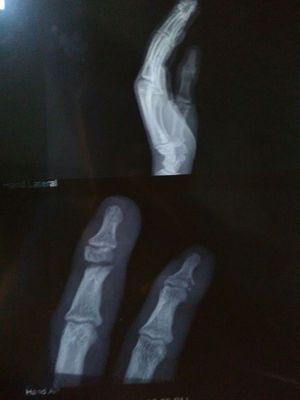

Fracture

Ortho

Phalanx